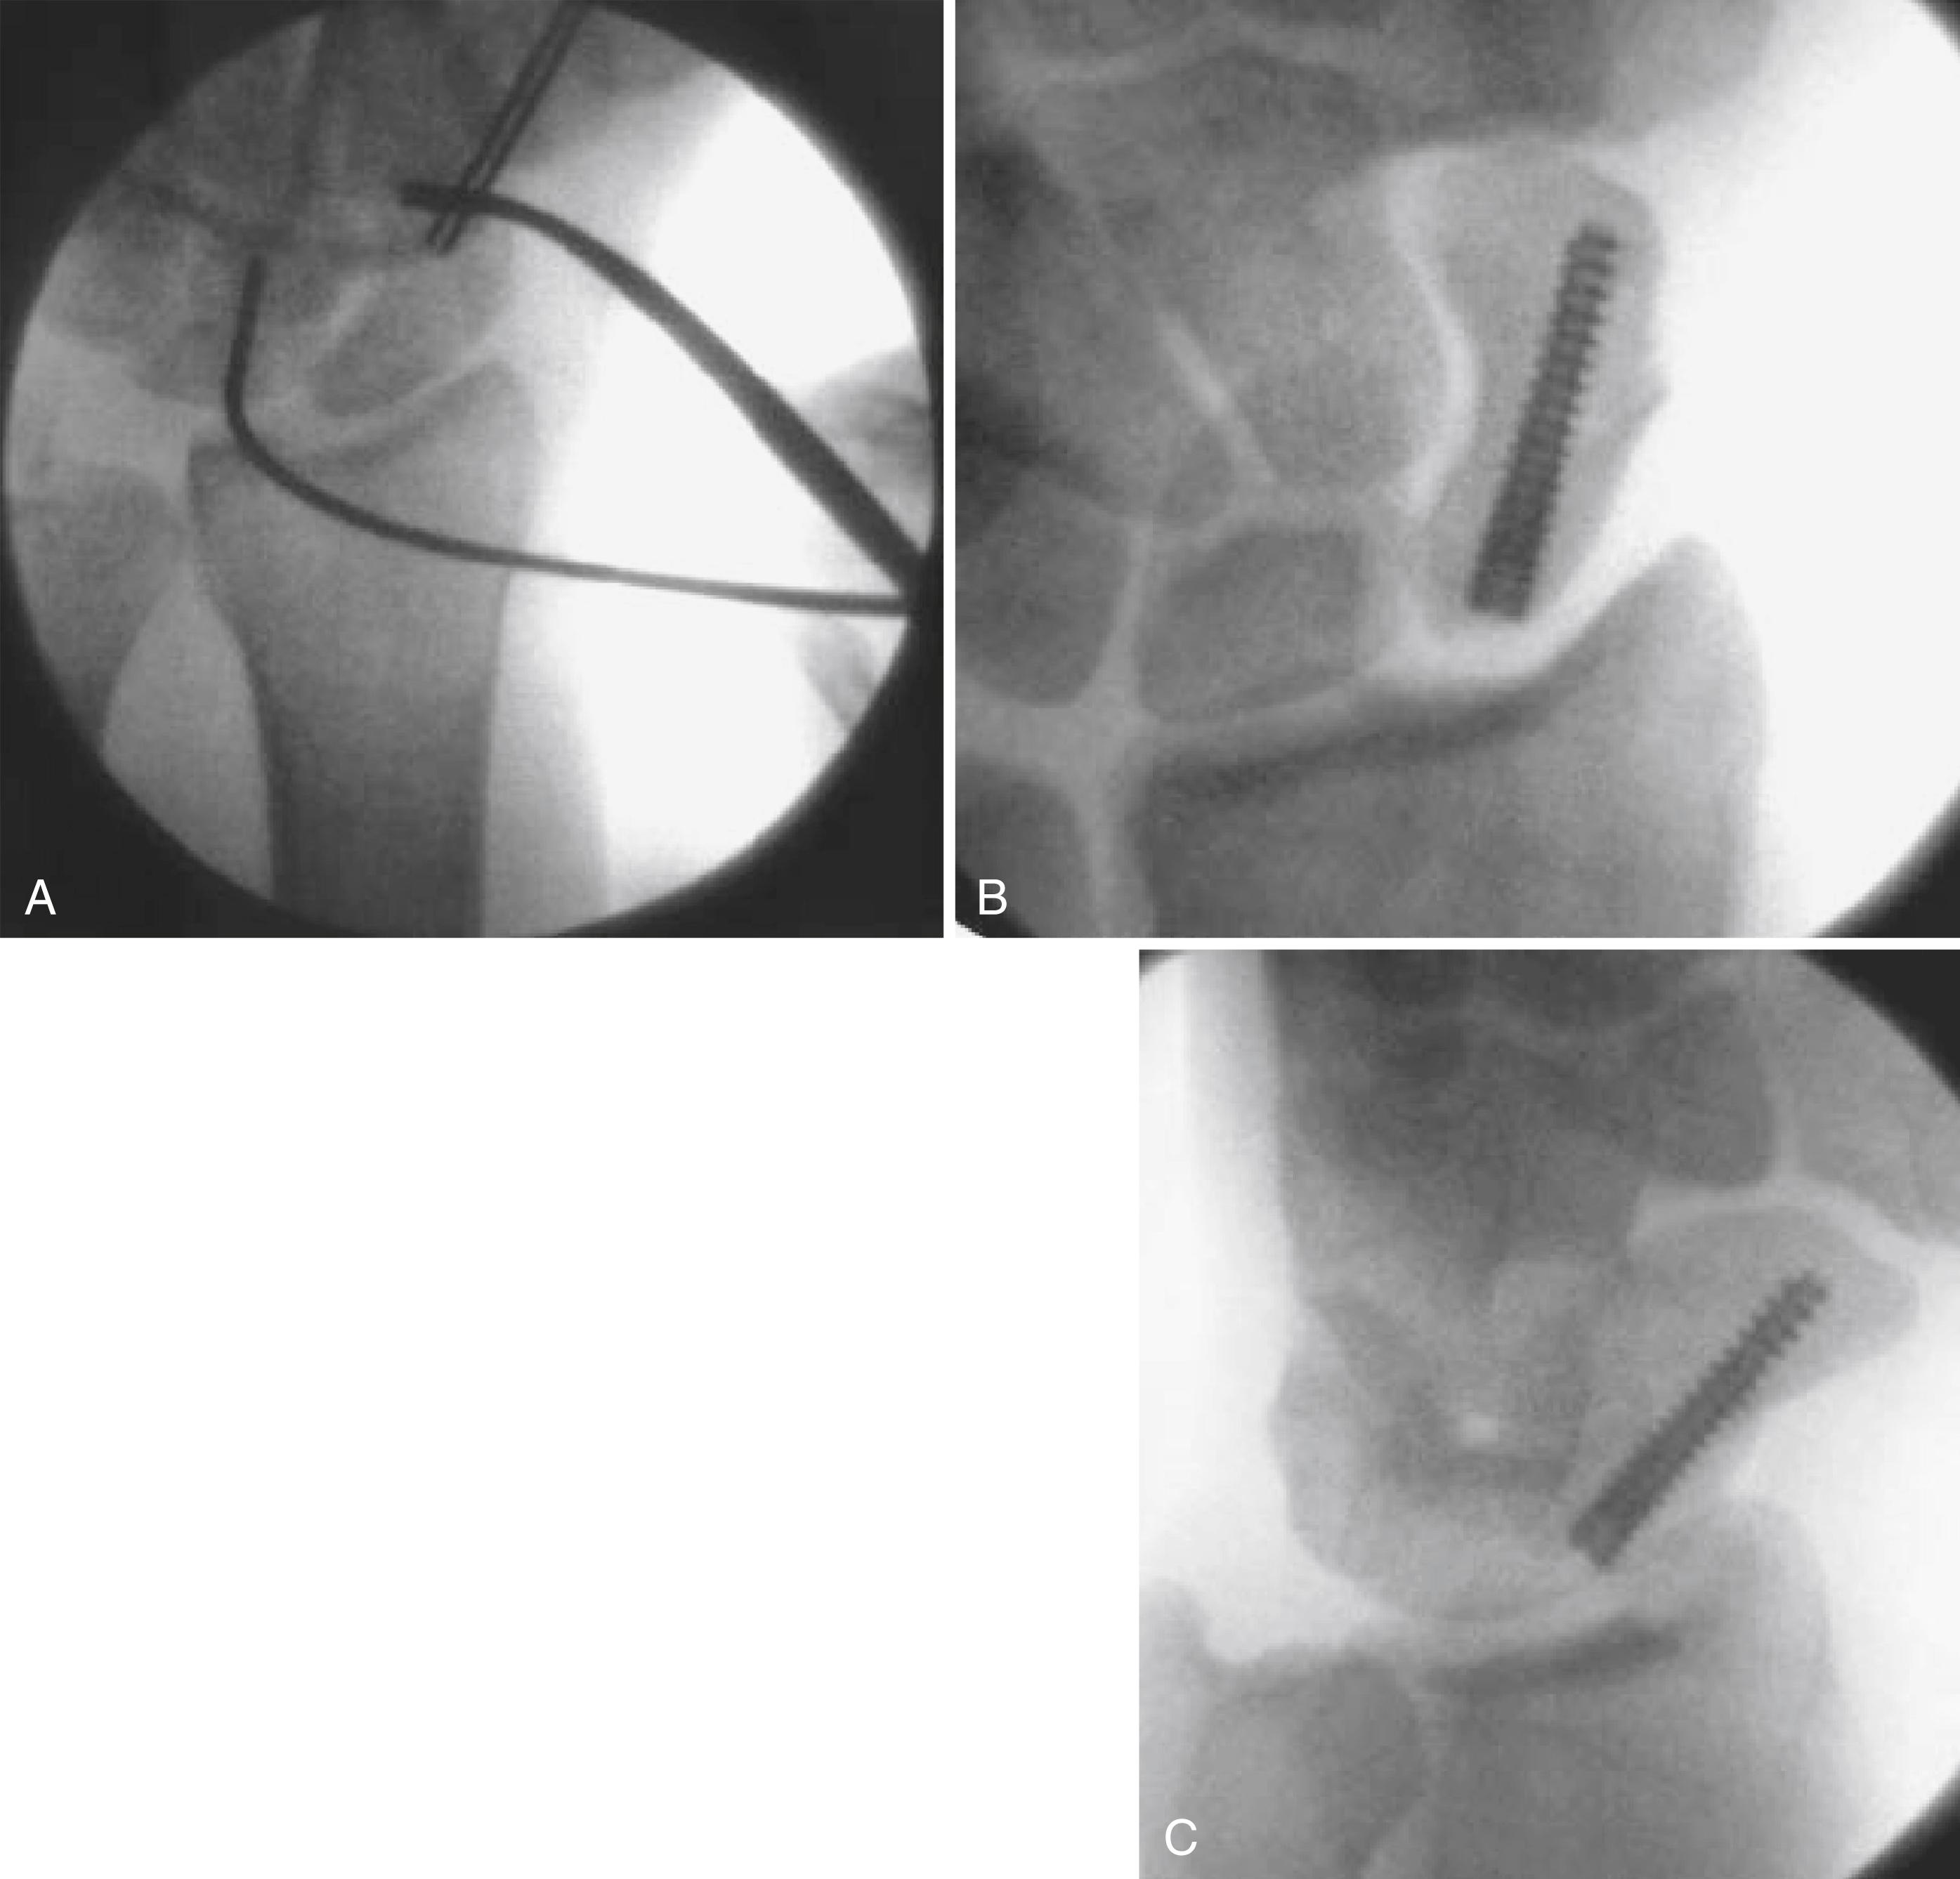

Arthrography of the wrist (triple injection when indicated) ( Fig. 69.13 )

FIGURE 69.13, Fluoroscopic spots during arthrogram. A, Needle in place, start of contrast injection. B, End of contrast injection, at point of slight patient discomfort; contrast material is confined to radiocarpal joint. C, With ulnar deviation, contrast material passes into midcarpal joint between lunate and triquetrum (arrowheads), indicating lunotriquetral ligament tear. D, On follow-up overhead view, contrast material fills midcarpal joints, including scapholunate joint from its distal aspect, making it difficult to see whether scapholunate or lunotriquetral ligament is torn. Small defect (arrowheads) between contrast material in scapholunate space and radiocarpal space indicates intact scapholunate ligament.